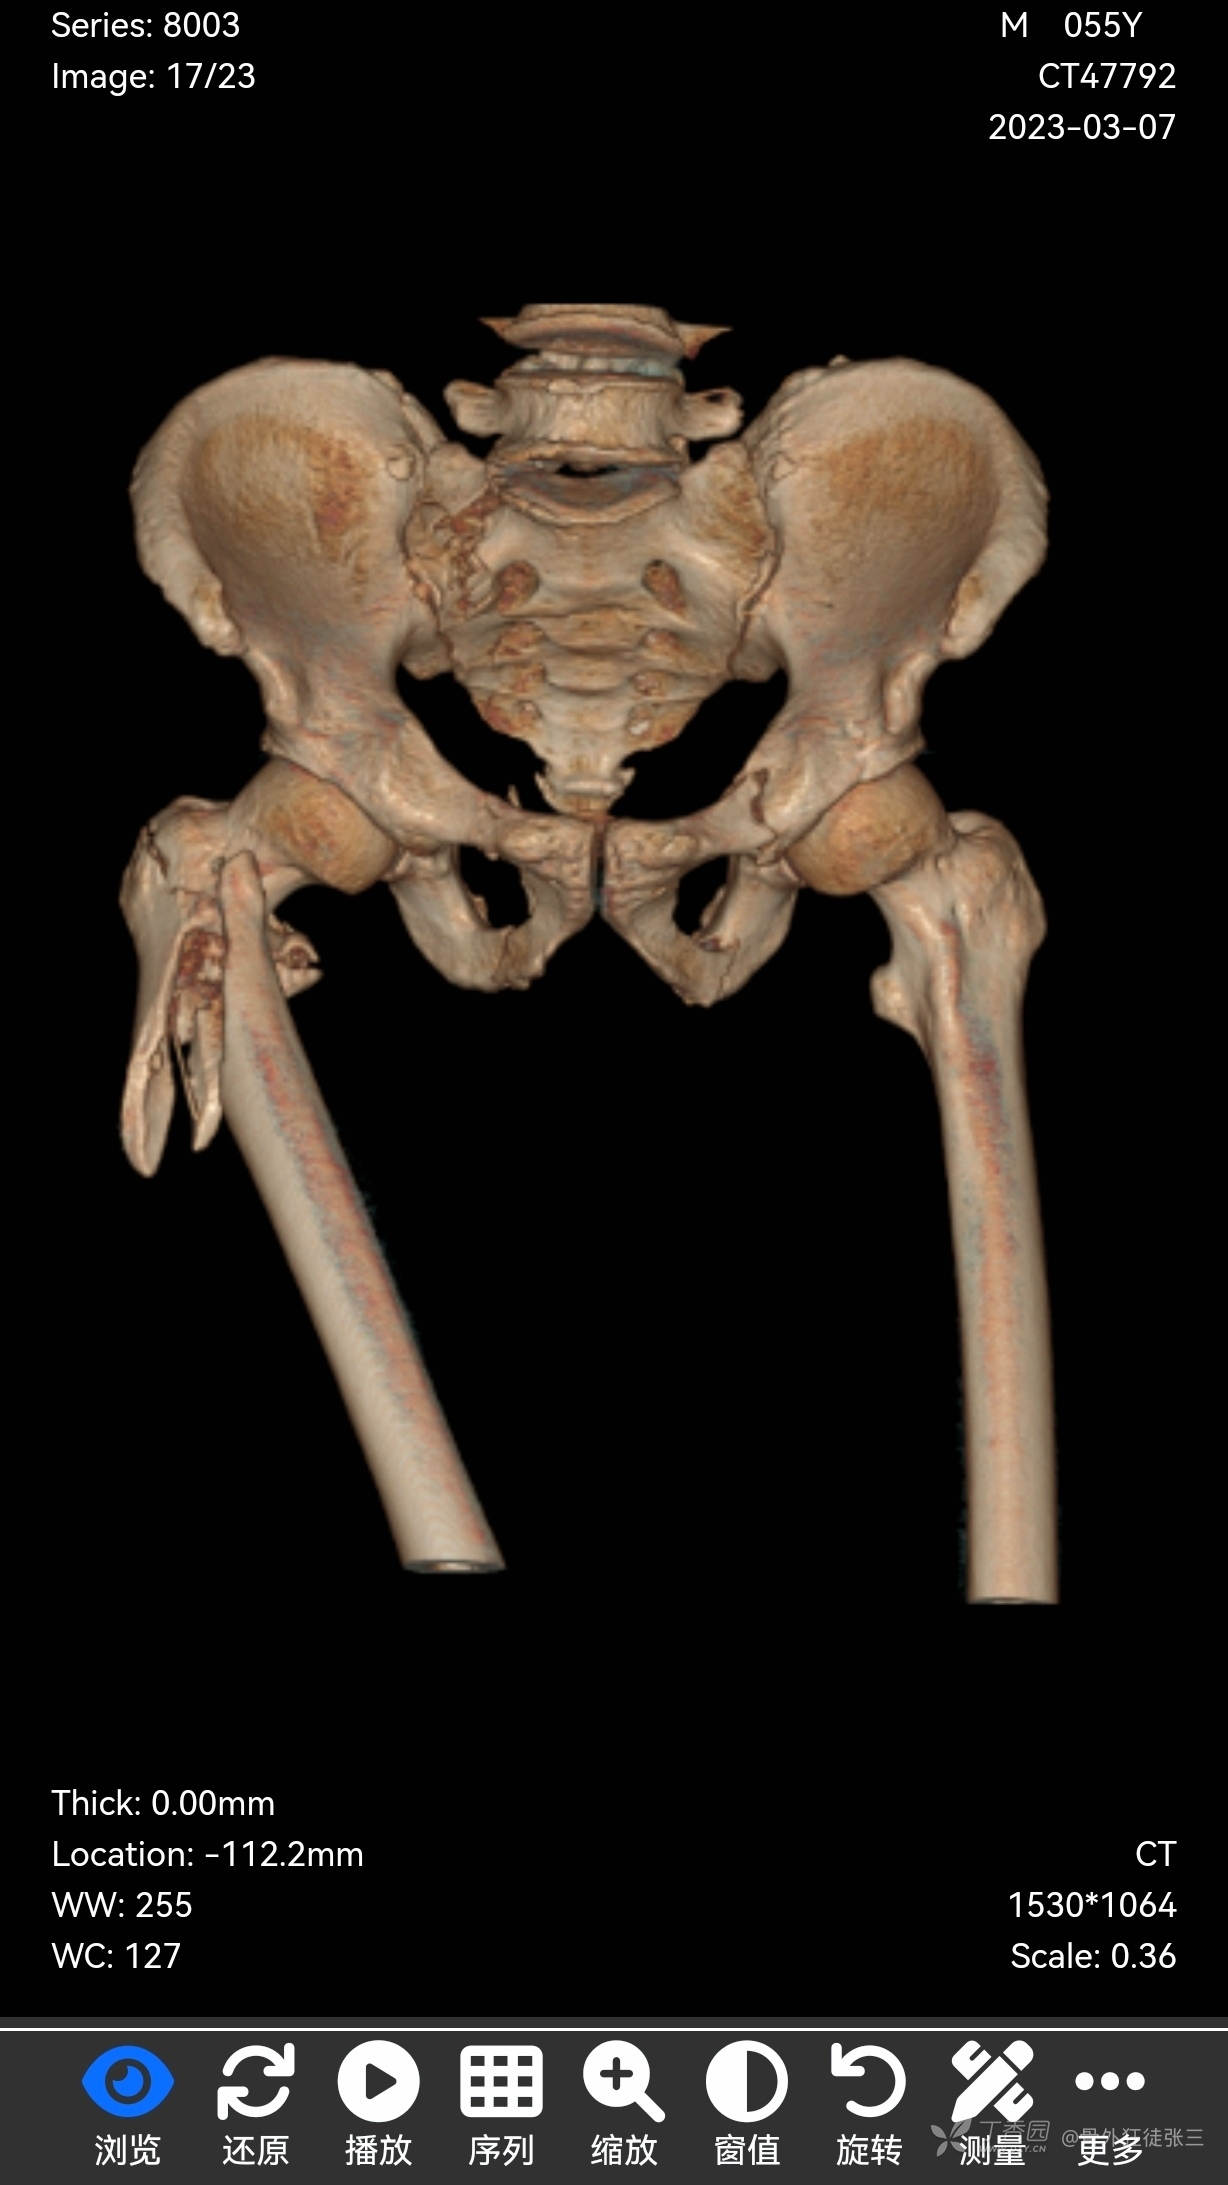

1,右股骨近端粉碎性骨折

8,骨盆多发骨折

CT示:右侧第5肋、胸骨、右侧髂骨、骶尾骨、右侧股骨颈、右股骨上段、左侧髋臼、双侧耻骨、双侧坐骨骨质连续性中断,部分断端错位,可见多发游离小骨片影。 右侧肘关节明显脱位,肱骨小头、肱骨滑车及桡骨小头多处骨质连续性中断,断端错位并分离,周围见多发游离小骨片影,周围软组织肿胀。 右侧舟骨、月骨骨质连续性中断,断端无明显错位。右侧豌豆骨向掌侧移位,可见骨质断裂。 左侧跟骨骨质连续性中断,断端错位,见多发游离小骨片影,周围软组织肿胀。右足诸骨骨质未见明显异常

检查结论: 1.双肺坠积性肺不张;右侧第5肋骨骨折;胸骨骨折

4.骨盆多发骨折;右侧肘关节脱位并肱骨滑车、肱骨小头、桡骨小头粉碎性骨折